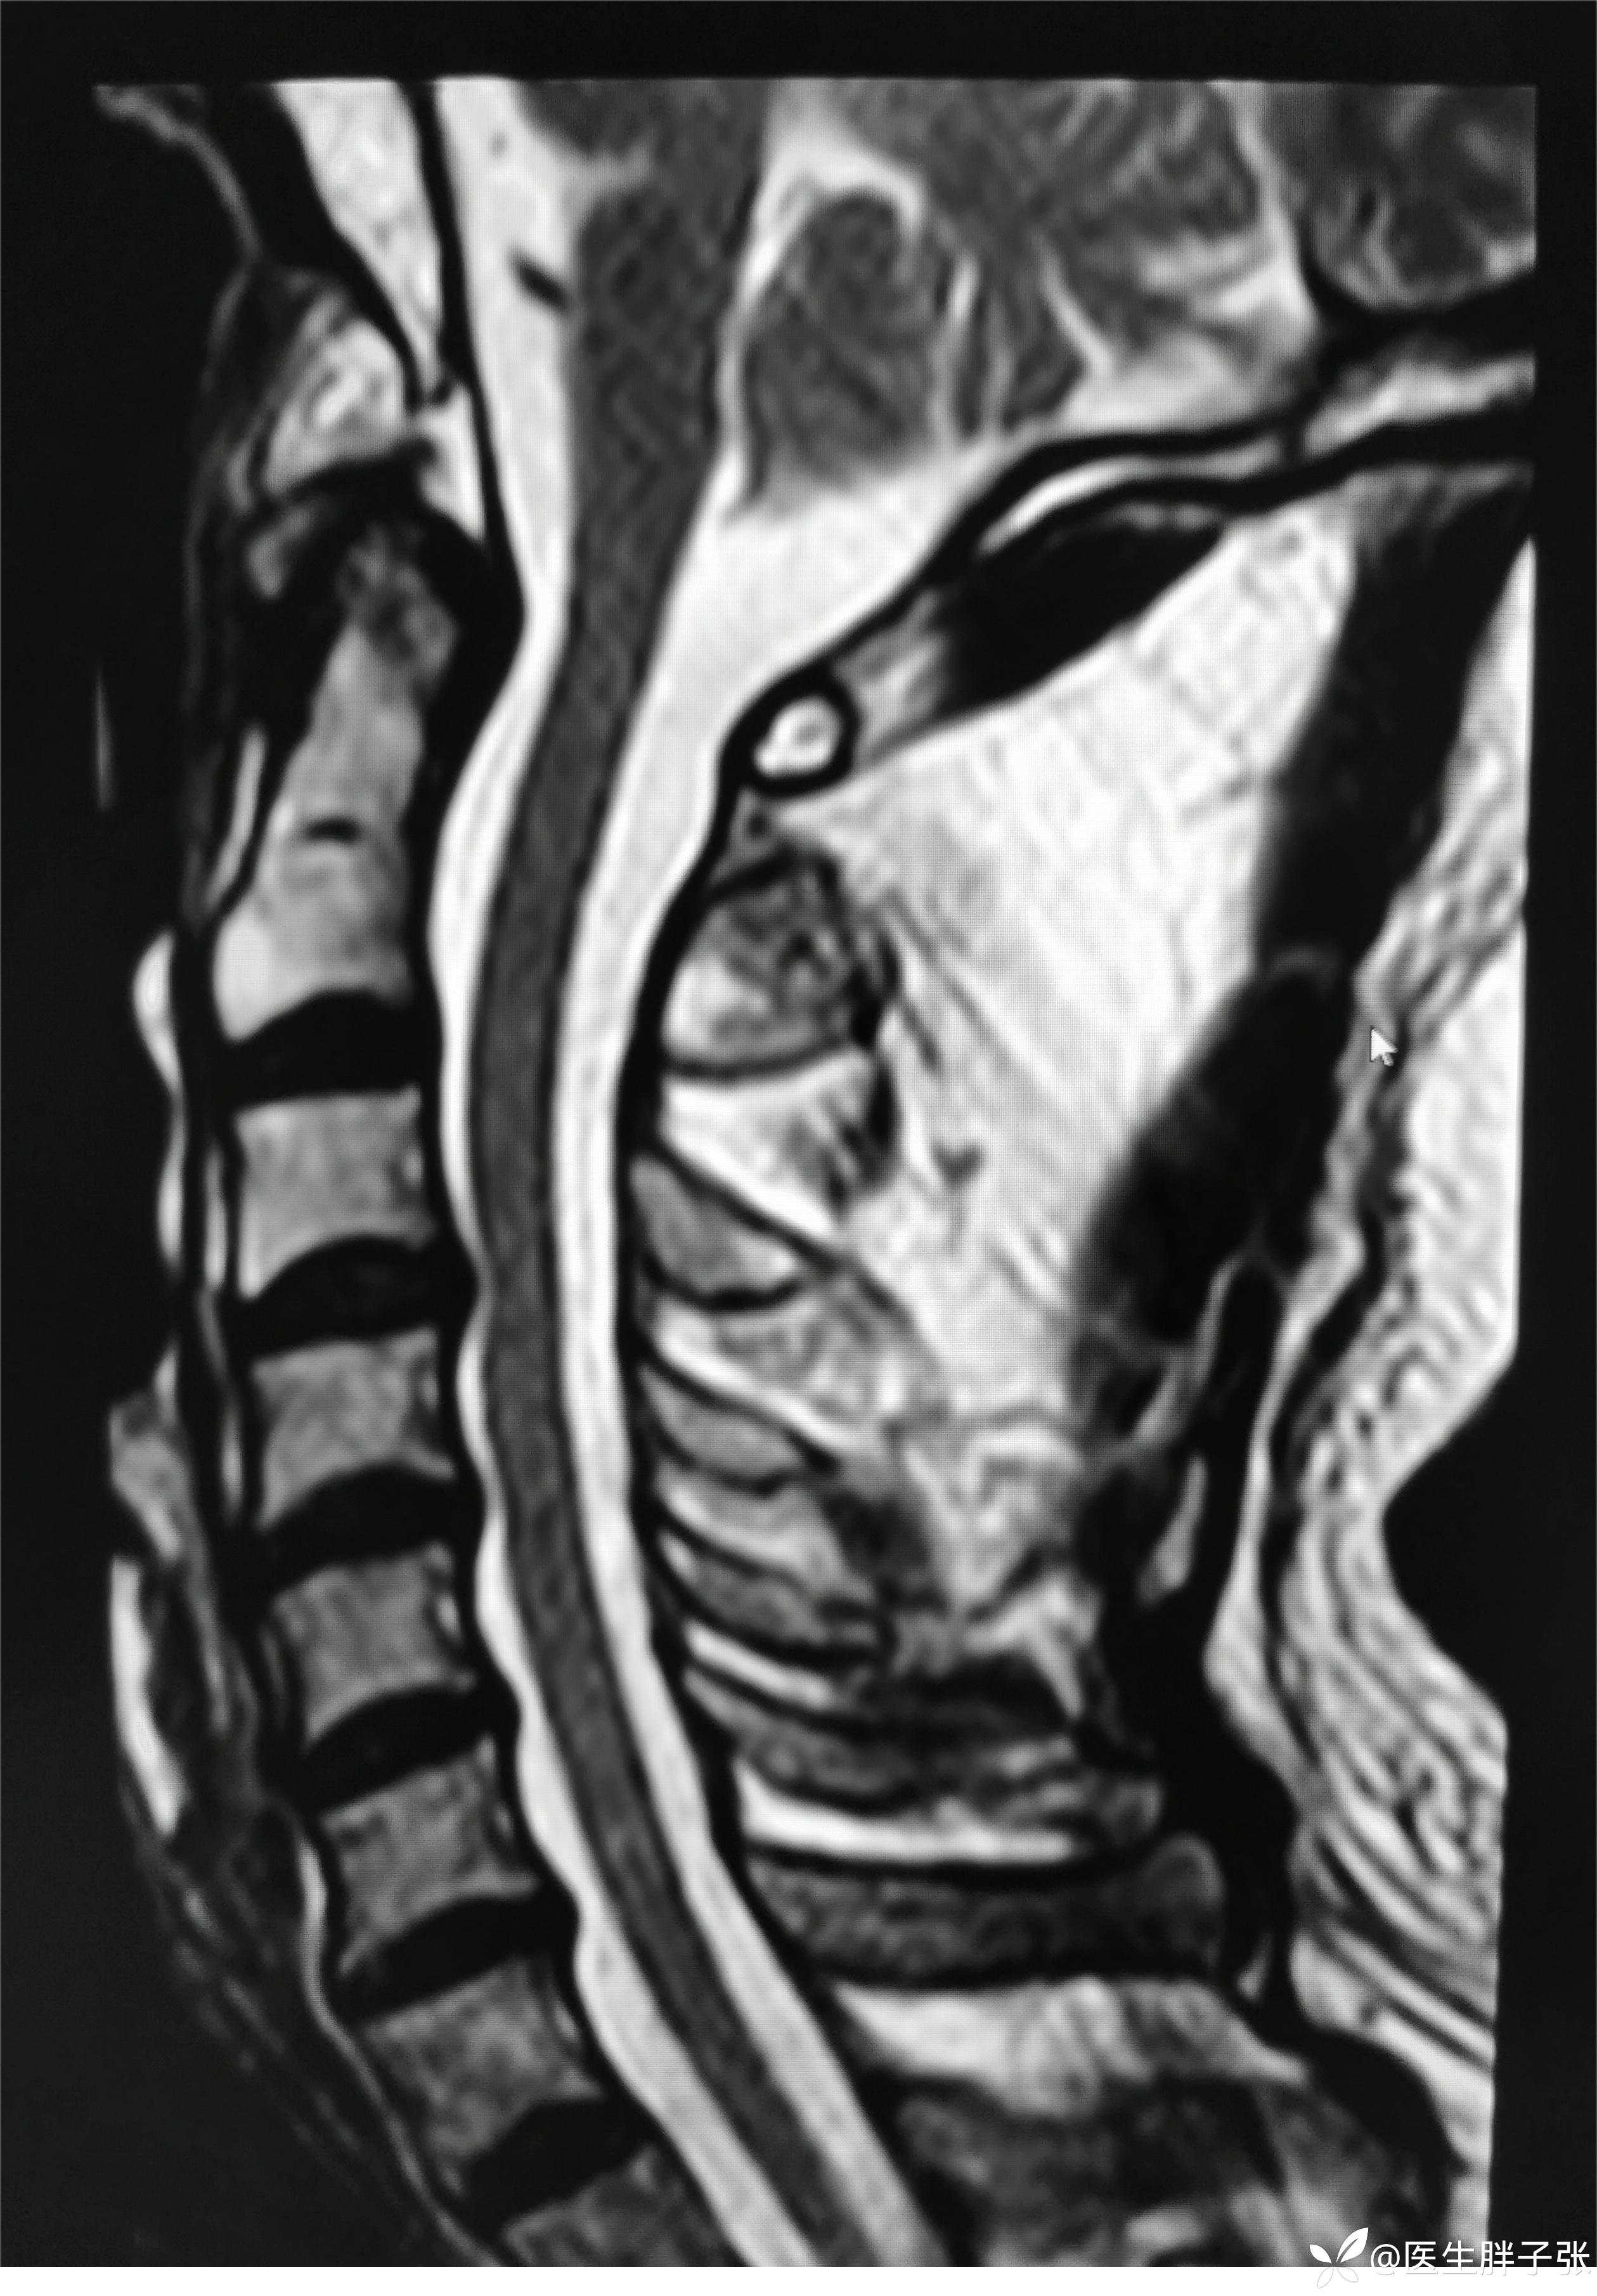

颈椎MR回报

头颈部CTA提示左侧椎动脉闭塞、右侧椎动脉开口中度狭窄、左侧颈内动脉动脉瘤。

查房意见:颅脑MR存在顶叶新近梗死,椎动脉作为责任血管的梗死可能性大。患者存在前驱感染,需除外颅内感染、自免脑、副肿瘤可能。